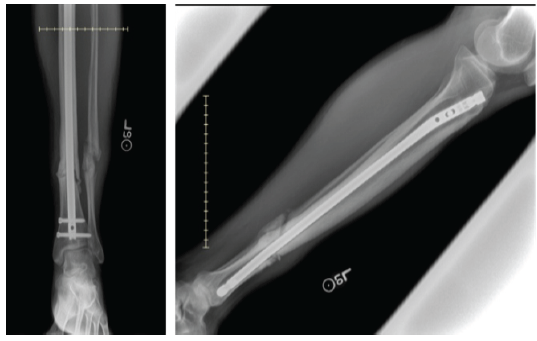

At 4 months, radiographs demonstrated delayed union, as noted in Fig. 2. The proximal interlocking screws were removed to allow dynamization. Six months later, persistent non-union was present, with continued pain and difficulty bearing weight. He subsequently underwent exchange intramedullary nailing with interlocking, fibular osteotomy, local bone grafting, and debridement of the pseudoarthrosis site. Despite these procedures, serial radiographs over the following months showed no evidence of progressive healing, as seen in Fig. 3.

Figure 3: Radiographs prior to final surgery showing fibular pseudoarthrosis and tibial non-union despite prior interventions.